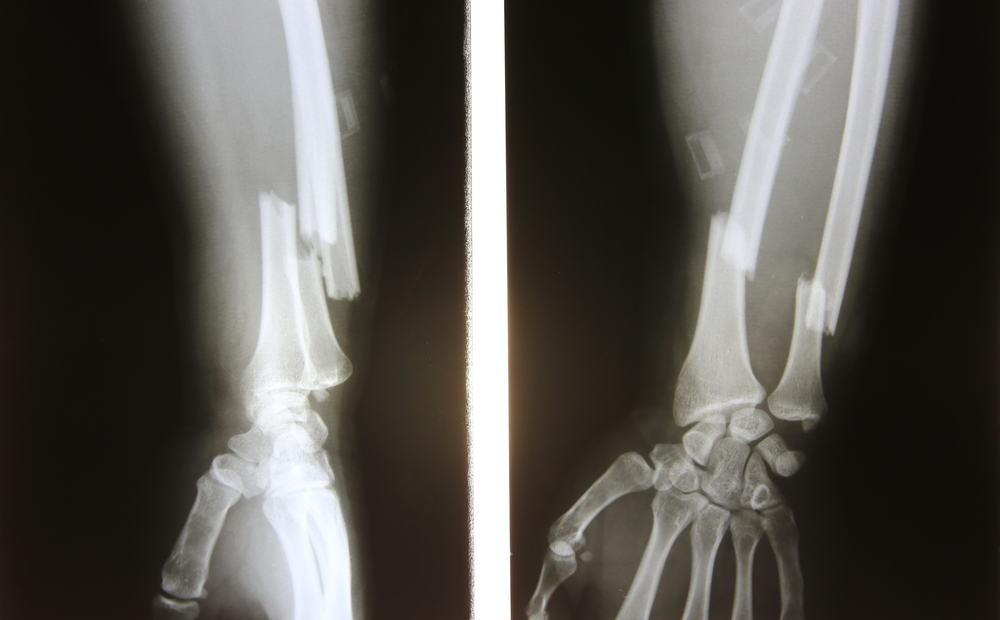

Theo quá trình ở trên thì xương có cơ chế tự chữa lành bằng cách tự nối lại với nhau. Tuy nhiên, khi quá trình này bị gián đoạn hoặc không theo đúng quy trình như bình thường hoặc xương chưa được nối lại với nhau ở đúng vị trí, hoặc lệch khỏi vị trí ban đầu xương đang trong giai đoạn lành có thể có cử động bất thường hoặc không ổn định, do cơ bám lên xương (dưới dạng gân cơ) nên dễ bị chuyển động. Điều này có thể biểu hiện rõ ràng hoặc nhìn thấy thông qua phim chụp X-quang ở vị trí xương gãy.

Thông thường sau khoảng thời gian 3 tháng điều trị (trừ trường hợp người cao tuổi hoặc ở những người rối loạn chuyển chuyển hoá hoặc suy dinh dưỡng sẽ lâu hơn) thì trên phim chụp X-quang đã có thể thấy rõ ràng cấu trúc liền xương . Trong trường hợp xương không lành lại thì phim chụp theo dõi quá trình phát triển xương sẽ thấy rõ.